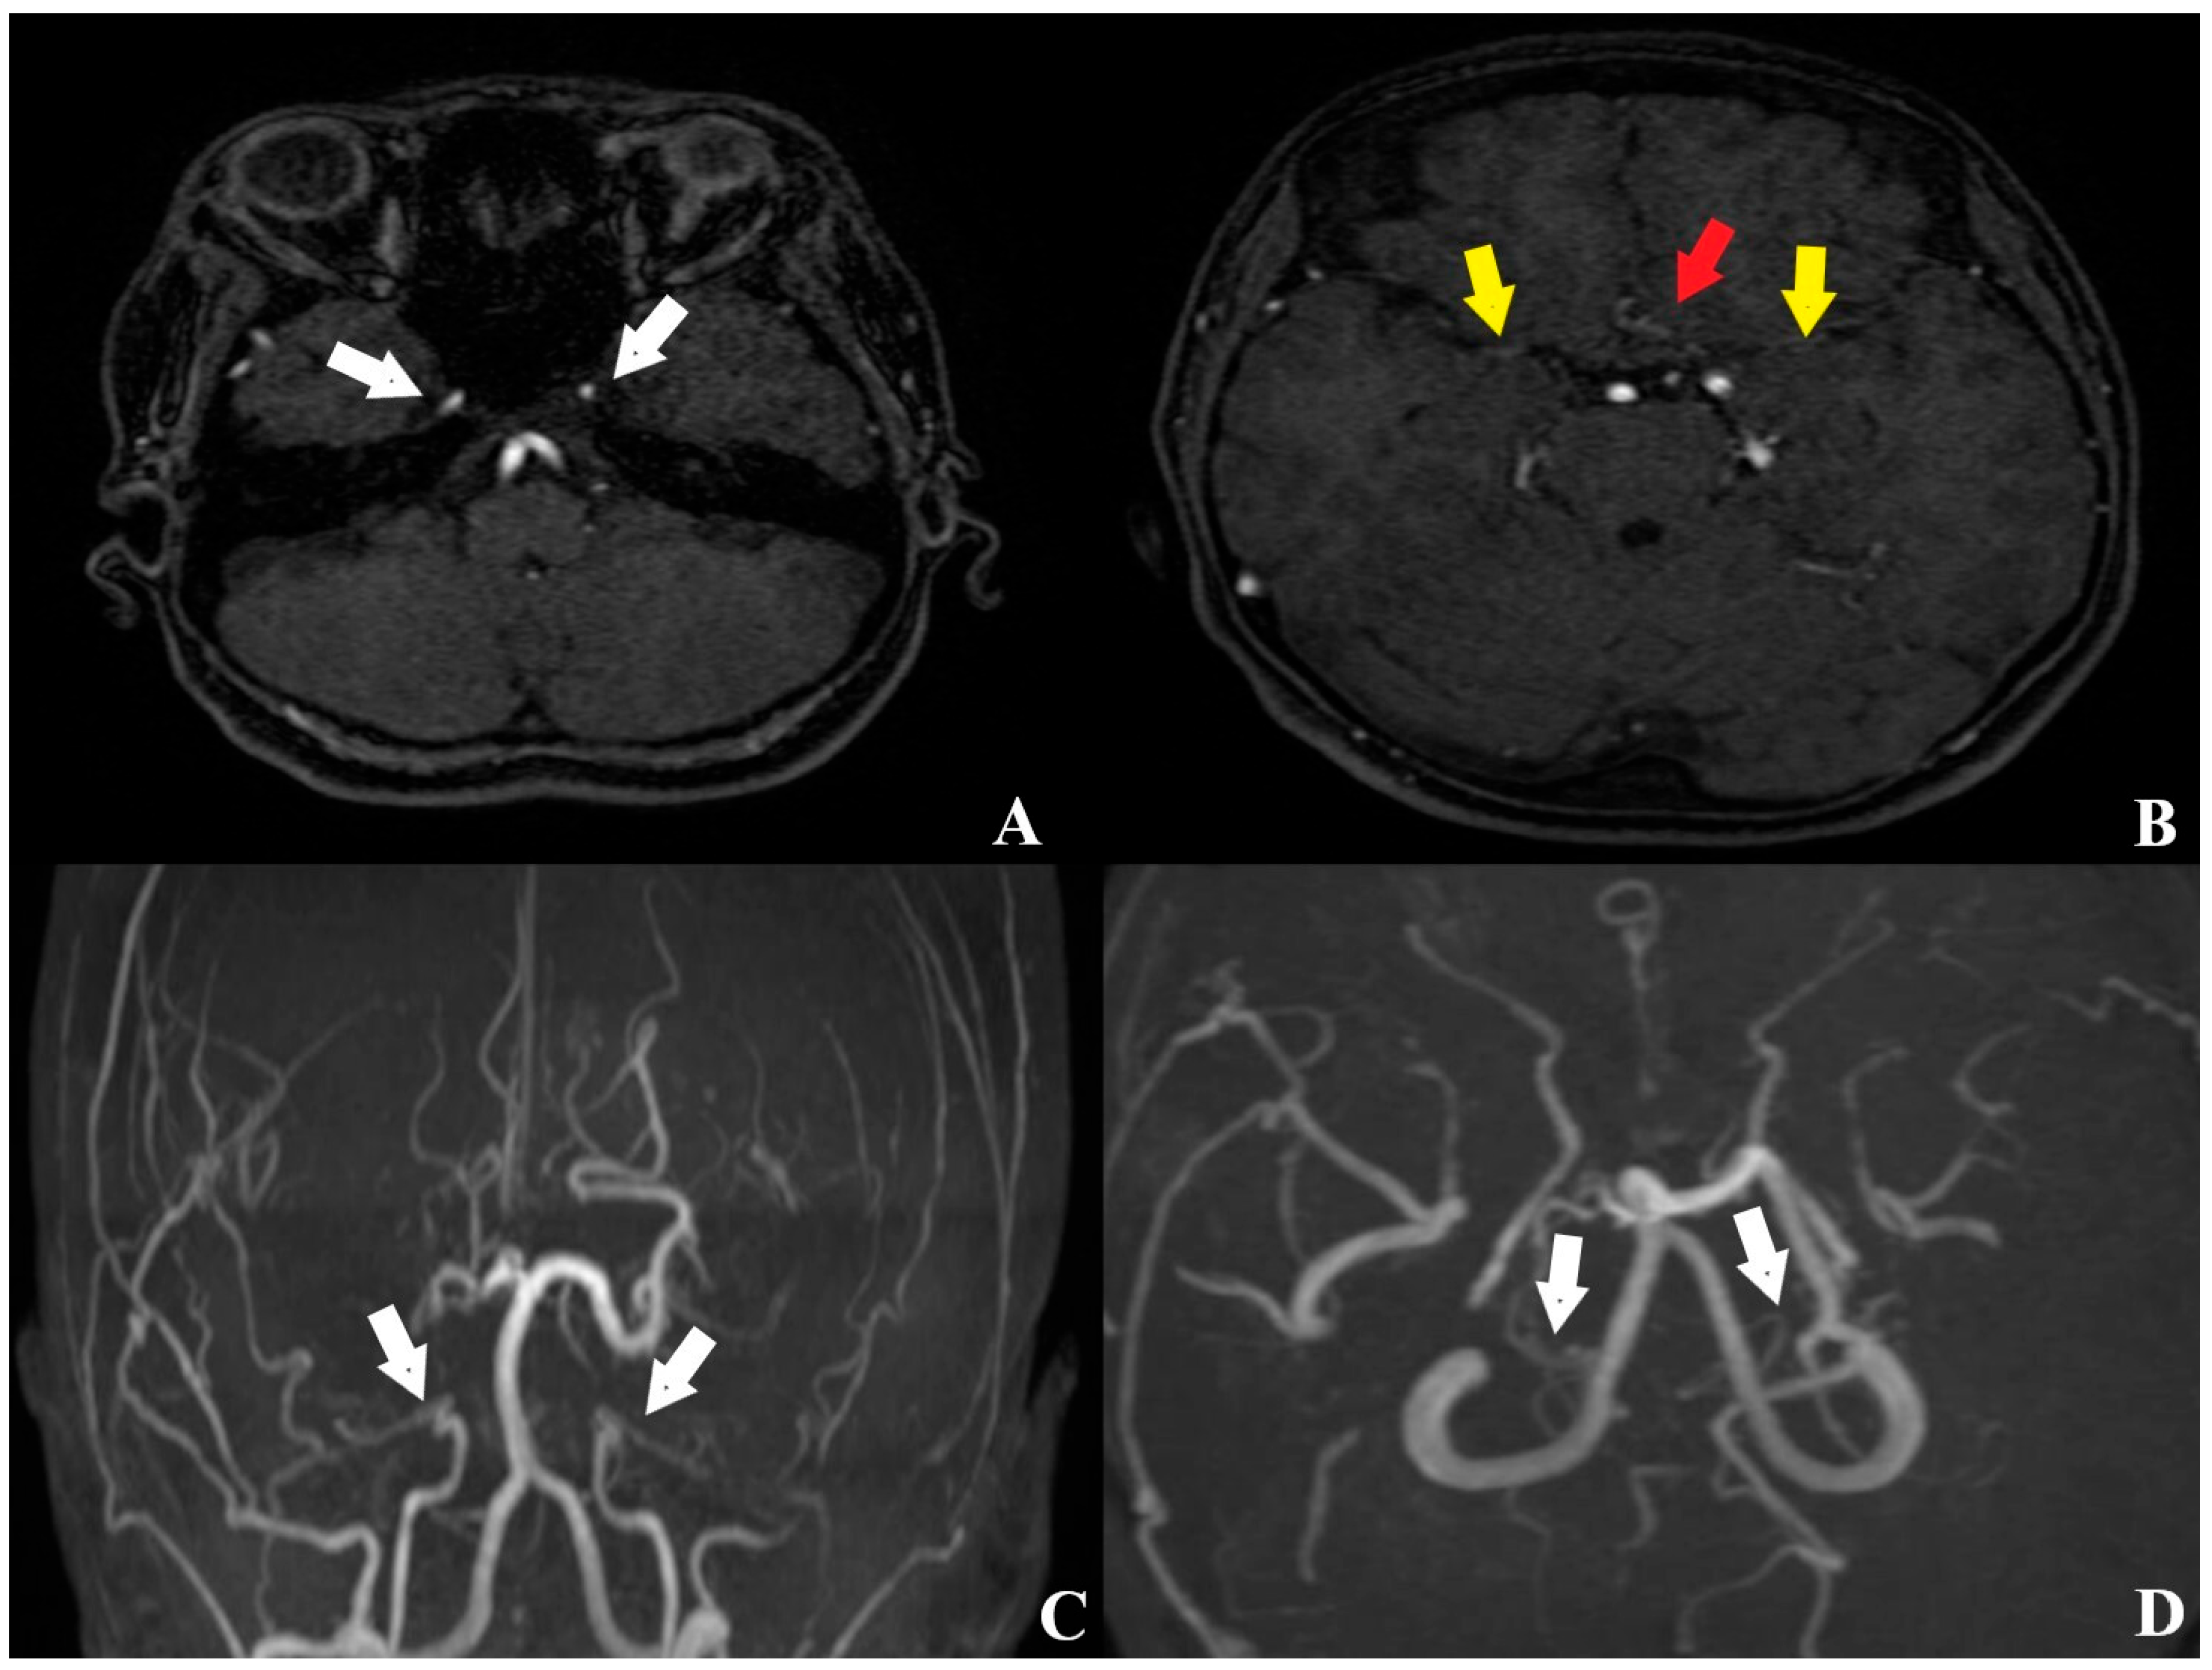

2. Case Description